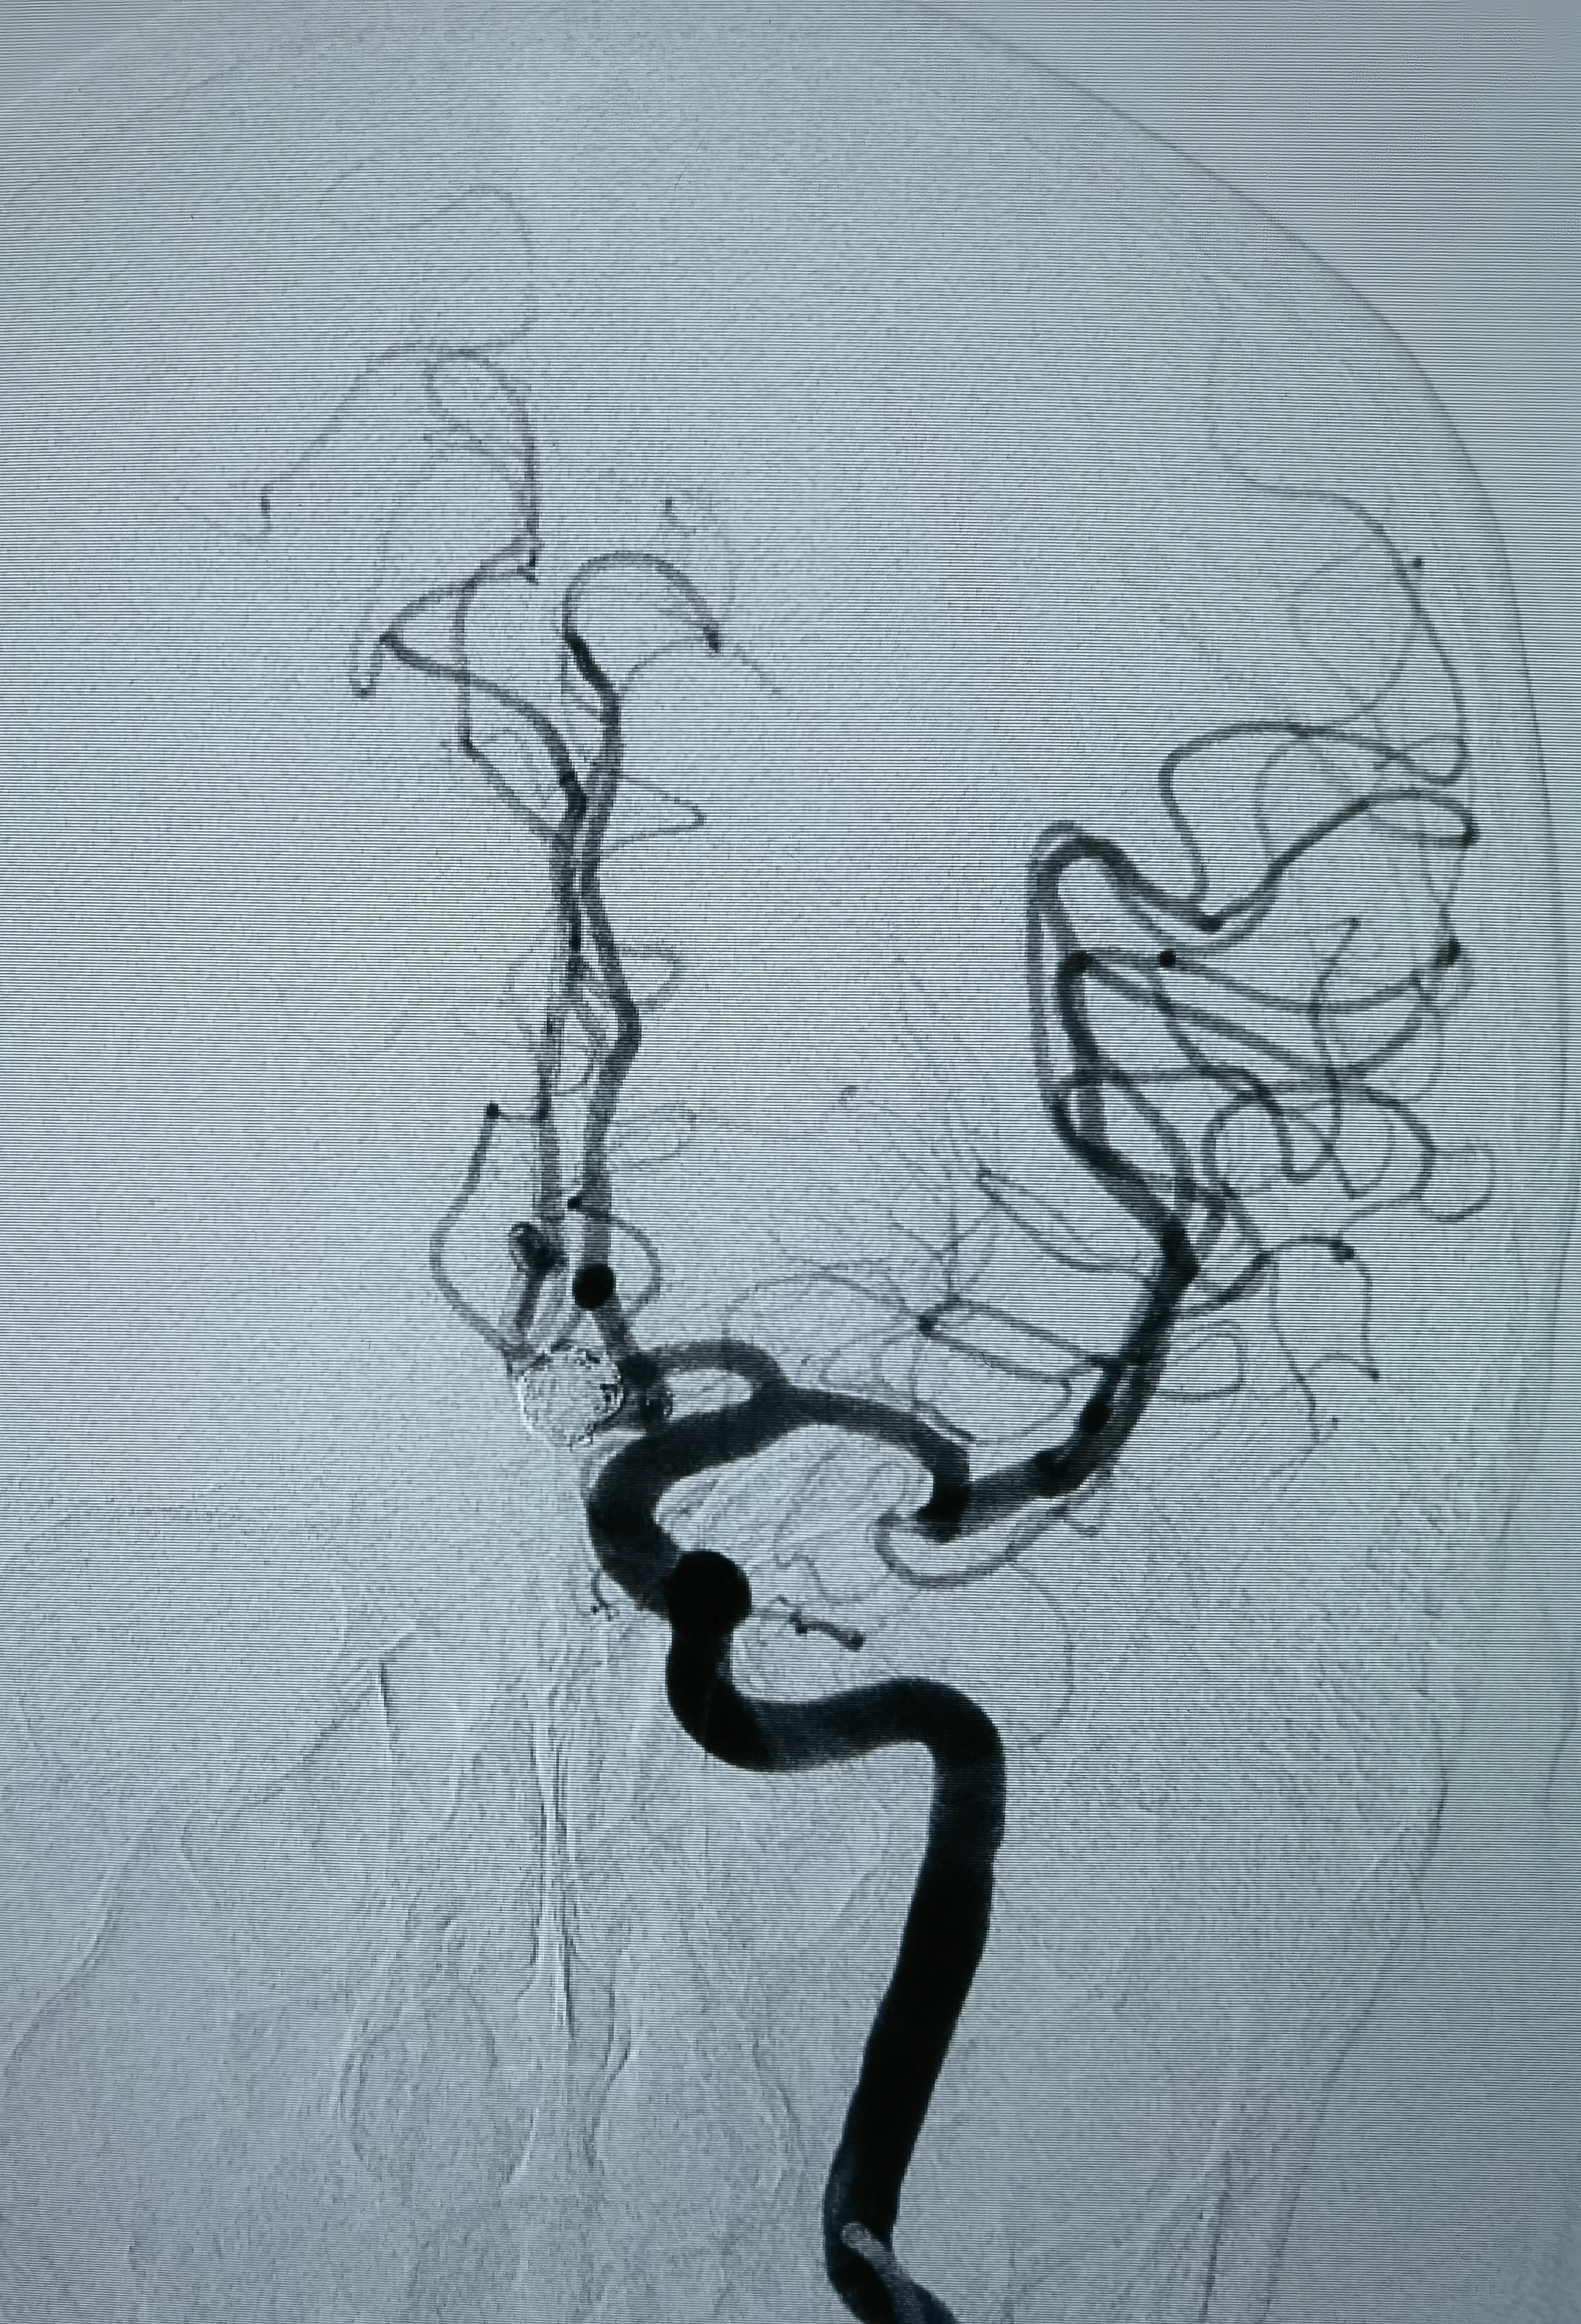

工作位造影

Atlas支架释放后微导管进入瘤腔,双微导管栓塞

术后造影